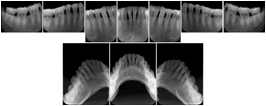

Intra-oral radiography typically involves acquisition of multiple images of various parts of the dentition. Many digital radiographic systems offer customized templates that are used for displaying the images in a study on the screen. These templates may also be referred to as mounts or view sets. The Structured Display Object represents a standard method of encoding and exchanging the layout and intended display of Structured Displays. A structured display object created in this manner could be stored with a study and exchanged with images to allow for complete reproduction of the original exam.

In most standard cases, images are oriented in structured layouts. These structured displays are useful to be shared between providers for reference purposes.

Table OO.1.1-1 shows structured display standard templates, where Viewset ID is based on the Japanese Society for Oral and Maxillofacial Radiology (JSOMR) classification provided by JIRA (Japan Medical Imaging and Radiological Systems Industries Association, www.jira-net.or.jp). Expected or typical teeth to be imaged location, region and designation codes are based on ISO 3950-2010, Dentistry - Designation system for teeth and areas of the oral cavity. For all the hanging protocols listed in OO.1.1-1, the value to use for Hanging Protocol Creator (0072,0008) is "JSOMR" and the value to use for Hanging Protocol Name (0072,0002) does not include "JSOMR" (e.g., "DL-S001A", not "JSOMR DL-S001A").